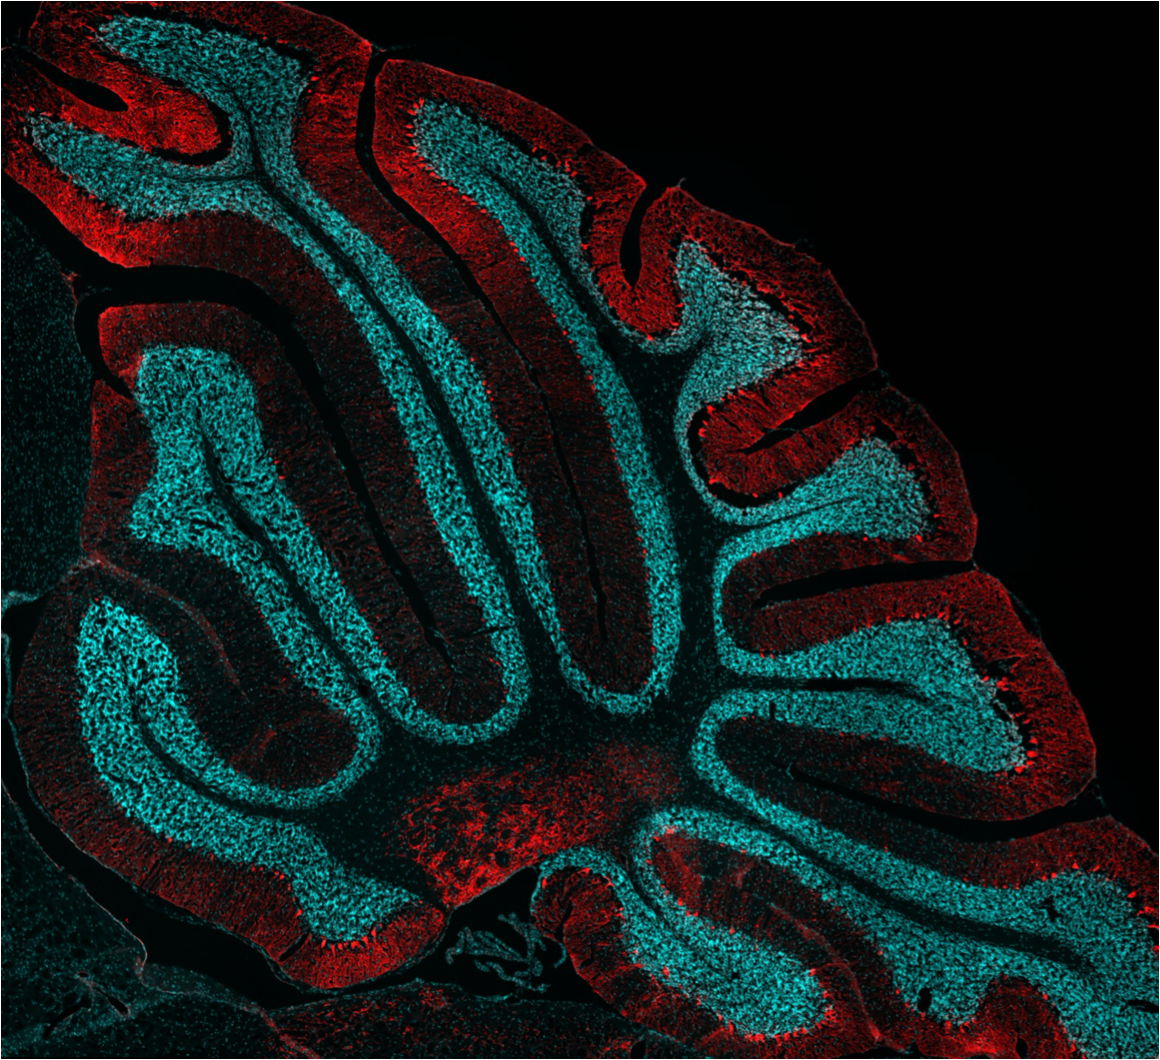

Ending the year on a high note with the acceptance of the lab’s first research paper. Congratulations to Jens and the team, and a big “Thank you” to our collaborators. Click on the figure for the full text.

Read our recent paper on the molecular mechanisms of cerebellar inhibitory neuron development.

Our latest paper is published in Science Advances.

Injury-induced ASCL1 expression orchestrates a transitory cell state required for repair of the neonatal cerebellum

Read the paper